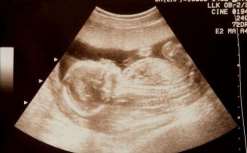

589 卵泡监测备孕有没有必要监测卵泡?备孕是否需要监测卵泡?接下来本文就为大家详细介绍一下。 备孕期间监测卵泡是有必要的,只 […]

备孕有没有必要监测卵泡?备孕是否需要监测卵泡?接下来本文就为大家详细介绍一下。 备孕期间监测卵泡是有必要的,只 […]